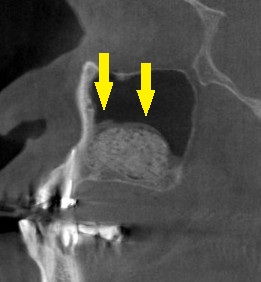

インプラント治療であれば、4歯ないところへ、2本のインプラントを埋入して、3歯回復を目指したいのですが、CTで見ると、特に2本目のインプラントを埋入したいところは、骨が非常に薄い状態でした(下の写真上段右)。

ワイドインプラントでも対応が困難と考え、サイナスリフトという骨造成をまず行って、骨量を確保することを提案させていただきました。

下の写真下段が手術後のCTです。